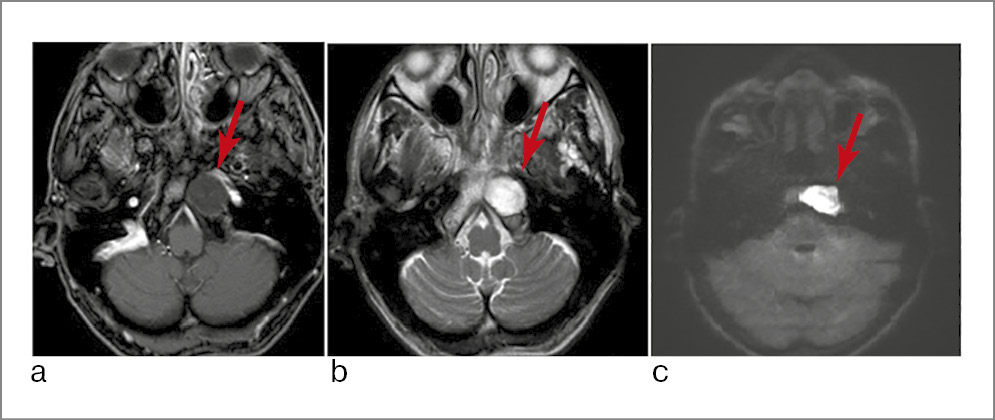

Рис. 7. КТ височных костей: определяется объемное образование петрокливальной области с разрушением костного канала горизонтального отдела левой сонной артерии, левого ската: а – аксиальная проекция; b – коронарная проекция.

Рис. 8. МРТ головного мозга: а – гиподенсивный сигнал в Т1-режиме; b – гиперденсивный сигнал в Т2-режиме; c – ограничение диффузии в NON EPI DWI области верхушки пирамиды слева (указано стрелками).